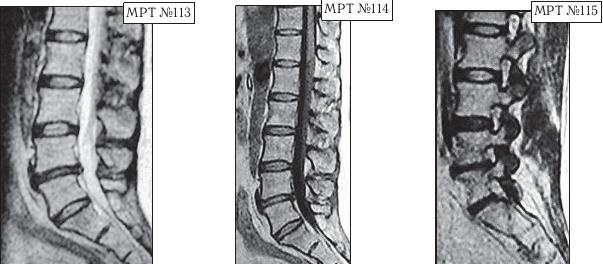

На МРТ № 108 состояние шейного отдела позвоночника пациента через 11 месяцев после дискэктомии с межтеловым спондилодезом в сегменте СIV—СV Наблюдается постхирургическая травма спинного мозга на данном уровне хирургической фрезой, кифозирование физиологического лордоза, стеноз позвоночного канала с блоком ликворных путей. На МРТ № 109 состояние шейного отдела позвоночника того же пациента через 23 месяца после дискэктомии с межтеловым спондилодезом в сегменте CIV-CV Наблюдается усугубление стеноза (абсолютный стеноз), спондилолистез (смещение вышележащего позвонка по отношению к нижележащему) СII— СIII, секвестрированная грыжа межпозвонкового диска CV—CVI. На данных снимках наглядно отображается, как подобные операции усугубляют биомеханические нарушения и тем самым способствуют развитию дегенеративно-дистрофического процесса в других сегментах позвоночника. Во время операции грыжу межпозвонкового диска в данном сегменте убрали. Но причины, которые как раз и спровоцировали образование грыжи, а именно биомеханические нарушения (дегенерация выше- и нижележащих межпозвонковых дисков, стеноз, кифоз), как были, так и остались! Несмотря на то что отдалённые последствия этой операции легко прогнозировались и полученный результат, как факт, абсолютно закономерен, подобные операции, к сожалению, как делались, так и делаются и, пожалуй, самое печальное, что и будут делаться дальше. Случаи послеоперационных рецидивов грыж межпозвонкового диска бывают разные, но причины, как правило, идентичны. Вот одна из типичных ситуаций. Врачи во главе с хирургом после хирургической операции пациента по поводу грыжи межпозвонкового диска в сегменте LV-SI в качестве профилактики посоветовали ему заниматься вытяжением позвоночника под собственным весом и укреплением мышечного корсета путём выполнения специальных упражнений на наклонной плоскости. Результат усердия пациента, последовавшего такому совету, можно наблюдать на МРТ № 110 (см. стр. 286). Исходя из анатомического и физиологического строения позвоночника человека и неизбежного действия законов физики, результат от такой «профилактики» вполне прогнозируем. Поэтому логично предположить, что врачи, посоветовавшие данному пациенту такую «профилактику», спровоцировавшую секвестрированную грыжу межпозвонкового диска в сегменте L^ — Ly, просто не знали о её последствиях. Если бы здоровье пациента позволило бы продолжить эти упражнения, то аналогичные осложнения неизбежно образовались бы и в вышележащих позвоночнодвигательных сегментах. ![]() На МРТ № 110 наблюдается состояние поясничного отдела позвоночника: секвестрированная грыжа межпозвонкового диска в сегменте LIV-LV с разрывом задней продольной связки, абсолютный стеноз спинномозгового канала. Но не спешите обвинять хирургов. Как бы это странно не звучало, это не их вина — они всего лишь удаляют часть ткани организма (грыжу). Ведь профессия хирурга заключается в знании и умении оказать пациенту своевременную хирургическую помощь, а вот послеоперационным восстановлением и «профилактикой» должны заниматься врачи-реабилитологи. Даже самые лучшие хирурги в мире, в совершенстве владеющие своей специальностью, за пределами операционной становятся обыкновенными людьми, которым, как и многим, свойственен относительный процесс познания. Требовать от них большего, это значит требовать от человека абсолютного процесса познания. Если вы считаете, что на это способен любой человек, попробуйте начать с себя. Гораздо хуже, когда врачи-реабилитологи в качестве «профилактики» дают такие «советы», вот это уже можно назвать профессиональной безграмотностью. Вот ещё случаи послеоперационных рецидивов грыж — естественной реакции организма, когда проблема решается однобоко — всего лишь с помощью хирургической операции в поражённом сегменте без общего восстановления биомеханики позвоночника.

На МРТ № 111 поясничного отдела позвоночника отмечается рецидив — грыжа межпозвонкового диска LIV-LV после трёх операций. Даже если прооперировать в четвёртый раз, то это всё равно не решит проблемы и не добавит здоровья данному пациенту, так как неизбежно возникнут осложнения в вышележащих сегментах LI—LII LIII—LIV в силу биомеханических нарушений в позвоночнике и выраженных дегенеративно-дистрофических изменений в указанных сегментах. На МРТ № 112 поясничного отдела позвоночника отмечается рецидив — секвестрированная грыжа межпозвонкового диска в сегменте LIV-LV после четырёх операций. Здесь, как говорится, без комментариев. К сожалению, в жизни бывает так, что даже профессиональный специалист иногда вместо пользы может принести серьёзный вред пациенту, исключительно из-за шаблонного подхода. Как ни парадоксально это звучит, но это так. Приведу один пример по этому поводу. Ко мне на приём привели женщину. Привели в буквальном смысле этого слова под руки, при этом она ещё дополнительно опиралась на тросточки. Первое о чём я подумал, когда увидел, с какой осторожностью её ведут и как она переставляет ноги, что у данной пациентки как минимум перелом позвоночника с травмой спинного мозга или как максимум — опухоль в спинномозговом канале. Но в данном случае причина оказалось совсем иной. На протяжении последних десяти лет у пациентки периодически возникали боли в поясничном отделе позвоночника. Она к ним привыкла и не переживала по этому поводу, так как боли были умеренные, быстро проходили и довольно легко переносились. Но полтора года назад, после физической нагрузки, появились сильные, тянущие боли в ноге. Женщина вынуждена была обратиться в больницу по месту жительства. Пациентку направили к невропатологу, который, осмотрев её, сделал предположение, что возможно у неё «грыжа межпозвонкового диска» и направил женщину на МРТ. Так вот, сделав МРТ (МРТ №№ 113–115), женщина вернулась со снимками к невропатологу. Он ознакомился с результатами обследования и вместо того чтобы назначить ей консервативные методы лечения при таком диагнозе, направил её… на консультацию к нейрохирургу. Нейрохирург между прочим специалист высокого класса, с большим опытом работы, спасший много человеческих жизней. Однако и он, ознакомившись с результатами обследования, осмотрев пациентку, сделал вывод, что необходима срочная операция по удалению грыжи межпозвонкового диска в сегменте LIV-LV.